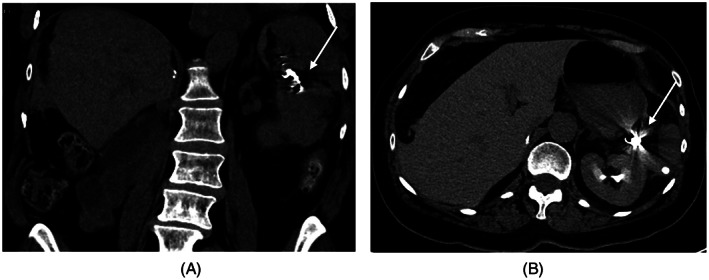

FIGURE 3.

CT SCAN images were obtained post coiling (arrow) of the ruptured splenic artery aneurysm (A) Coronal image; (B) Axial image

She had coil embolization of the splenic artery by intervention radiology (Figure 3). Her recovery was complicated by a post‐operative hematoma and elevated troponin, no intervention was required.